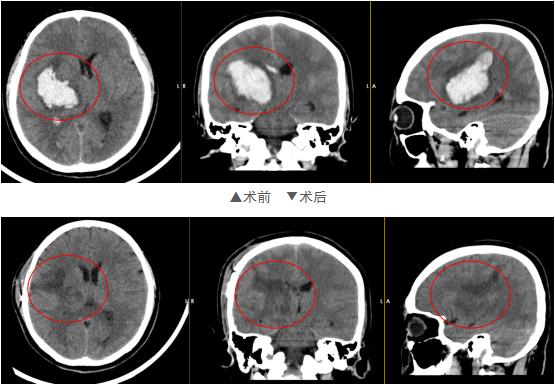

考虑到患者已经出现嗜睡状态,林涛团队急诊在全麻下行“内镜辅助下右侧基底节血肿清除”。术中依据导航准确定位血肿位置及进入方向,内镜引导下吸除血凝块约20ml,血性液体约10ml。清除血肿后,脑组织张力明显下降。

(术前及术后CT对比,提示血肿全清除)

住院治疗一段时间后,关某情况恢复得很快,生活能够自理。复查头颅CT提示原颅内血肿消失,胸部CT提示原吸入性肺炎明显改善。